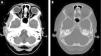

We present the case of a girl aged 9 years with high fever, right ear pain and otorrhea and ipsilateral temporal headache. The key findings of the physical examination were tender swelling over the right zygomatic arch, trismus and retroauricular erythema. The CT scan showed right mastoiditis with subperiosteal abscess in the temporal bone and a very small non-occlusive thrombus in the sigmoid sinus (Fig. 1). The salient laboratory finding was acute phase reactant elevation. Treatment was initiated with cefotaxime and clindamycin and achieved a favorable outcome. Saprophytic microorganisms were isolated in culture.

Computed tomography image. (A) Soft tissue window with intravenous contrast: right mastoiditis with temporal subperiosteal abscess measuring 3.5 mm and very small non-occlusive thrombus in sigmoid sinus. Asymmetrical enlargement of soft tissues indicative of reactive myositis in temporalis muscle. (B) Axial CT image, bone window, showing otomastoid fluid buildup.